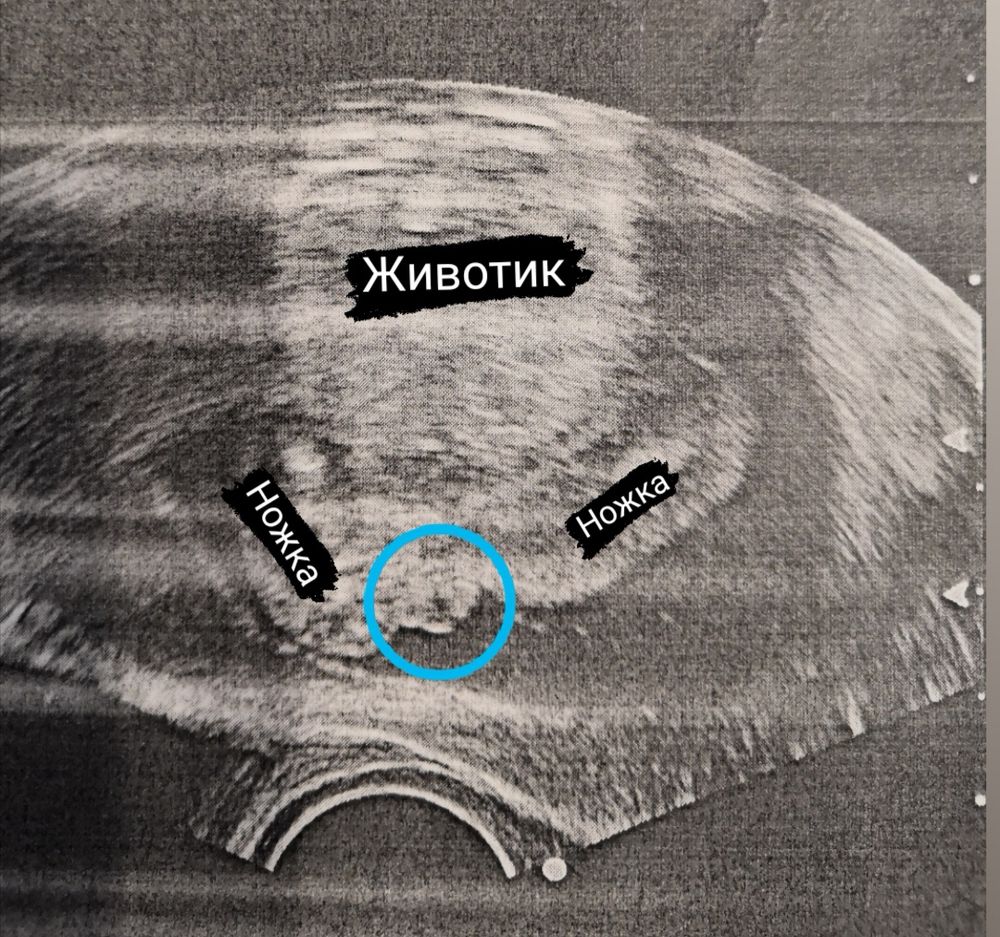

Как думаете кто? В синем кружке то самое место🥲это узи сделано в 18 недель, в 32 недели мне сказали, что девочка)